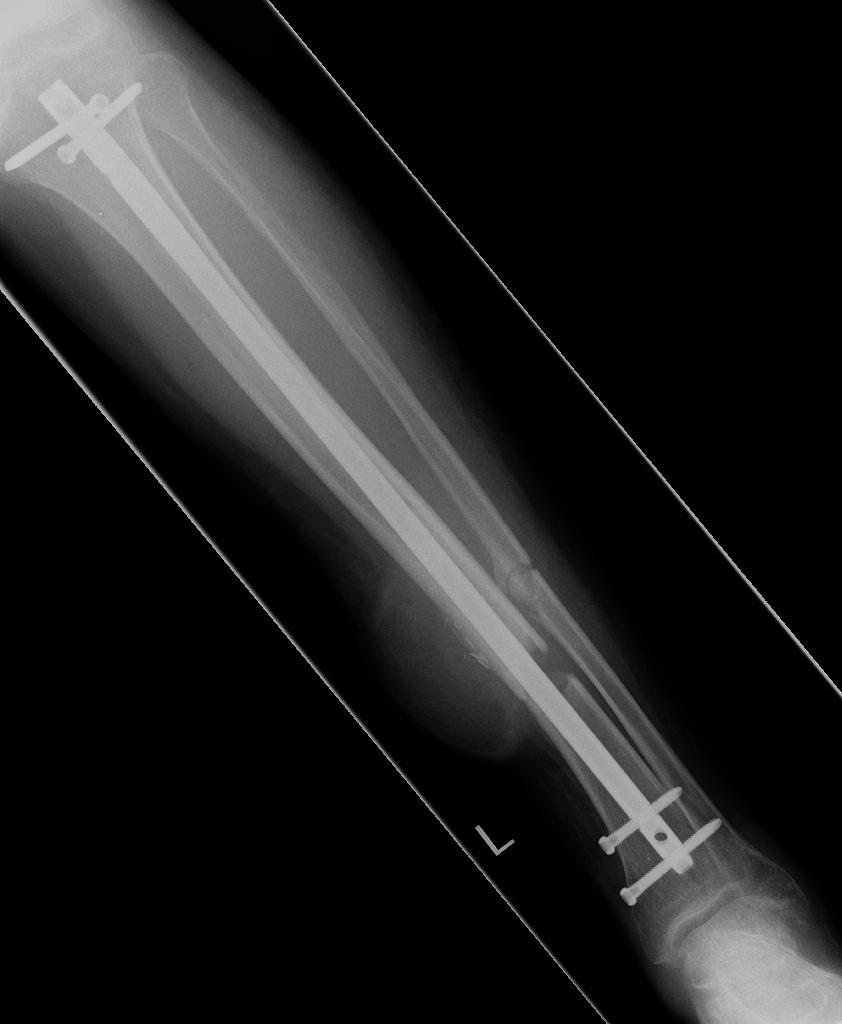

From news reports, Stephen was scooped up onto the hood of an SUV that was barreling down the bridge, flew into the air, thrown into the back end of a bus, and was dumped onto the road, hitting his head, fracturing his skull, neck, back, ribs, puncturing his lung – and shattering bones in his left leg, ripping part of his calf open.

Recovery was long and slow, taking years of physical therapy for Stephen to be able to walk again. He had seven operations on his leg. They had to keep repeating the surgery in order to get the bone to grow properly. A skin flap had to be taken from his right thigh to reconstruct his calf, which was completely ripped open.“The repetition was heartbreaking,” says Stephen. “We’d get our hopes up and then have to go back into surgery over and over again.”